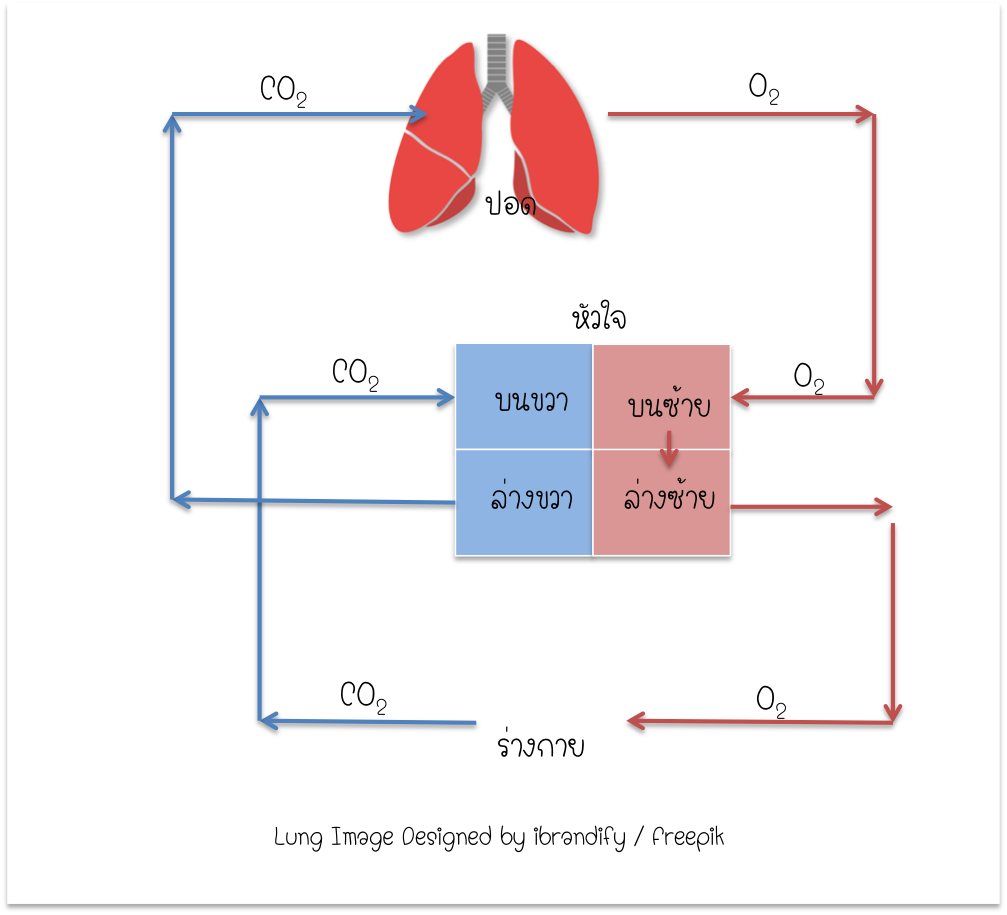

เพิ่มเติมความรู้ระบบร่างกายมนุษย์ (Body system Biology): 2015 การไหลเวียนของปอด ภาพประกอบสต็อก – ดาวน์โหลดรูปภาพตอนนี้ – ปอด – ระบบ …

การไหลเวียนของปอด ภาพประกอบสต็อก – ดาวน์โหลดรูปภาพตอนนี้ – ปอด – ระบบ … Heart Diagram กายวิภาคศาสตร์ร่างกายมนุษย์ระบบไหลเวียนโลหิตหัวใจ …

ระบบไหลเวียนโลหิตขนาดเล็กและใหญ่: วงจร วงกลมขนาดเล็กและขนาดใหญ่ของสิทธิ … สภาติวเตอร์ By TS Council

ระบบหมุนเวียนโลหิต 📝โน๊ตสรุประบบหมุนเวียนเลือด… – สภาติวเตอร์ By TS Council | Facebook